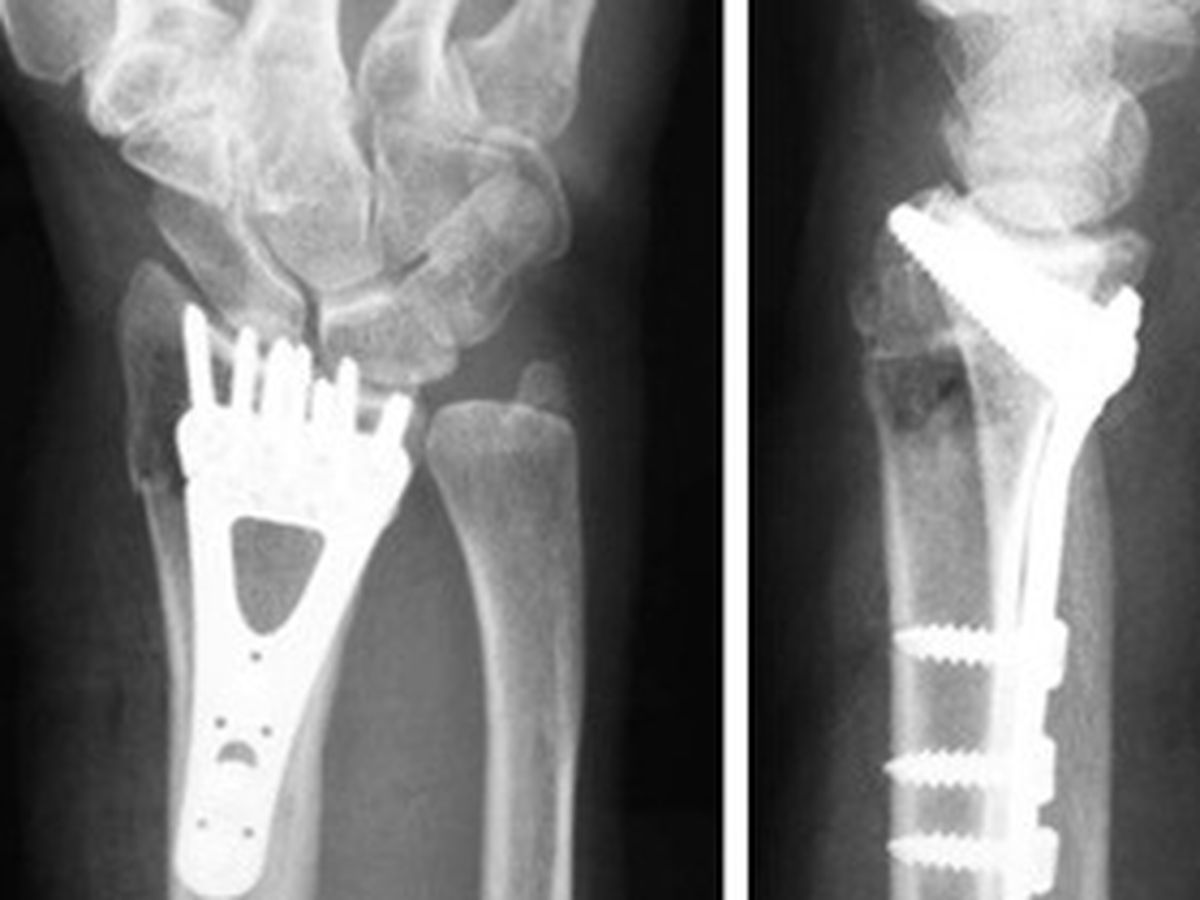

This past Tuesday 8/7 I had metal plate and screws put in right wrist. Yesterday, they performed the same procedure on my left wrist.